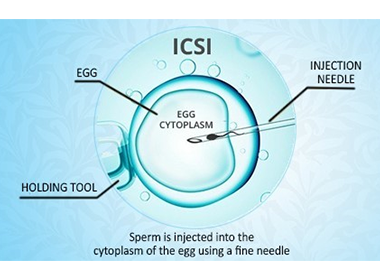

Intracytoplasmic Sperm Injection (ICSI)

An advanced IVF method where a single sperm is directly injected into an egg to aid fertilization.